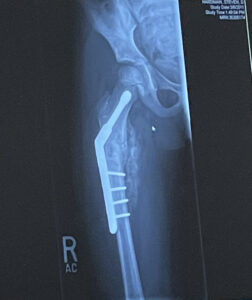

When he was just five years old, he had an ABC tumor in his right femur bone that caused a multitude of problems. He broke his femur bone three times, needed two rods, four screws and a plate put in his leg which necessitated five surgeries.

The doctors told his family they didn’t know if he was going to be able to walk normally again – let alone play sports.

It took him four years, but through sheer resiliency he was able to relearn how to walk. He started playing baseball again at the age of 11.